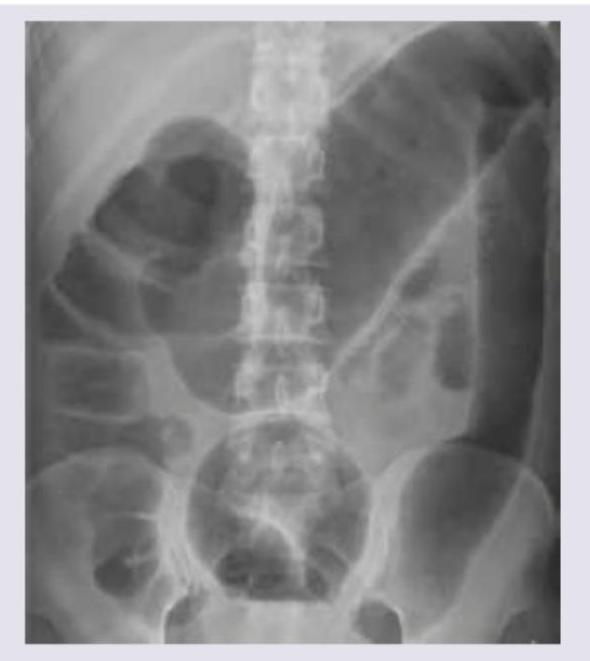

A 53 year-old woman with history of ulcerative colitis presents to the emergency department with a severe flare. The patient reports numerous bloody loose stools, and has been febrile for two days. Vital signs are: T 101.9 HR 98 BP 121/86 RR 17 Sat 100%. Abdominal exam is notable for markedly distended abdomen with tympani and tenderness to palpation without guarding or rebound. KUB is shown in figure A. CT scan shows markedly dilated descending and sigmoid colon with no perforations. What is the next best step in management for this patient?